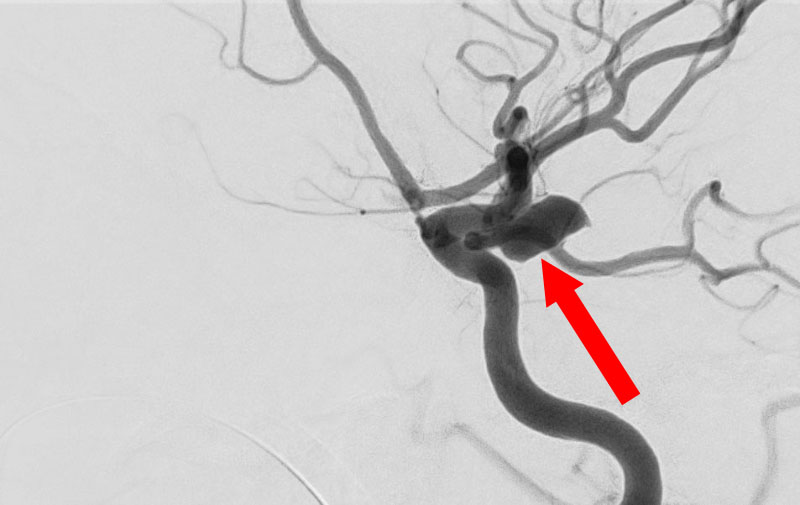

くも膜下出血

左中大脳動脈瘤破裂

40代

救急外来

No.1596 手術前

No.1596 手術中

No.1596 手術後